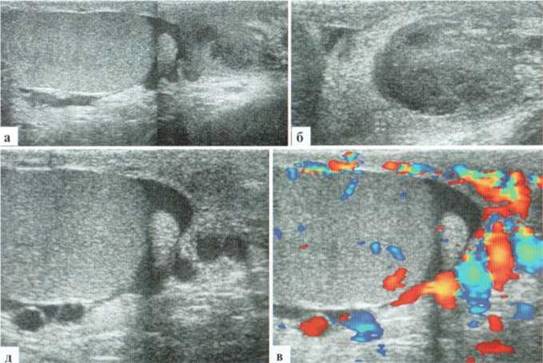

Антенатальный перекрут

Причина и точные сроки возникновения антенатального перекрута яичка у младенцев до настоящего времени не известны. В литературе имеются описания дородовой ультразвуковой диагностики перекрута яичка у плода с послеродовым интраоперационным подтверждением. В практической деятельности большинство новорожденных с антенатальным перекрутом яичка переводятся в профильное отделение на 2—3 сутки жизни, при этом дооперационное УЗИ выявляет грубые структурные изменения тестикул и отсутствие сосудистого рисунка в ткани яичка, что не оставляет надежд на благоприятный исход (рис. 2.6.I2).

Рис. 2.6.12. Антенатальный перекрут и некроз яичка: а, б — яичко плохо дифференцируется от окружающих тканей, бесструктурное, в оболочках определяется немного гетерогенного содержимого, сосудистый рисунок в паренхиме яичка не прослеживается; в, г — на операции: перекрут яичка, на разрезе яичко черное

При консервативной тактике ведения таких пациентов яичко постепенно склерозируется, при этом оно значительно уменьшается в размерах, в возрасте 2—3 месяцев едва достигает 6x5мм, паренхима его остается бесструктурной и аваскулярной (рис. 2.6.13).

Рис. 2.6.13. Исход антенатального перекрута яичка: а — на 2-е сутки жизни яичко размерами около 14x6 мм, неправильной формы, бесструктурное, аваскулярное, дифференцируется с трудом; б, в — в возрасте 2.5 месяцев яичко 6x4 мм, склерозировано

Казуистически редким является перекрут обоих яичек. Прогноз для ребенка в плане нарушения гормонального статуса и дифференцировки вторичных половых признаков серьезный (рис. 2.6.14).

Рис. 2.6.14. Антенатальный перекрут и некроз обоих яичек: а, б — поперечный скан мошонки. Оба яичка плохо дифференцируются от окружающих тканей, структура яичек гетерогенная, четко проследить контуры яичек невозможно, сосудистый рисунок прослеживается только в оболочках яичек; в, г — правое яичко; д, е — левое яичко